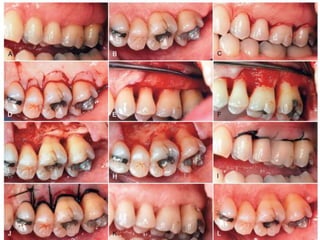

APICALLY DISPLACED FLAP

▸ Used for pocket eradication, widening the zone of

attached gingiva, or both

▸ Step 1: An internal bevel incision is made. To preserve

as much of the keratinized and attached gingiva as

possible, it should be no more than about 1 mm

from the crest of the gingiva and directed to the

crest of the bone

▸ Step 2: Crevicular incisions are made, and this is

followed by the initial elevation of the flap.

Interdental incisions are then performed, and the

wedge of tissue that contains the pocket wall is

removed.

▸ Step 3: Vertical incisions are made extending beyond

the mucogingival junction. If the objective is a full-

thickness flap, it is elevated by blunt dissection with

a periosteal elevator

▸ If a split-thickness flap is required, it is elevated via

sharp dissection with the use of a Bard–Parker knife

to split it. This leaves a layer of connective tissue,

including the periosteum on the bone

▸ Step 4: After the removal of all granulation tissue,

scaling and root planing, and osseous surgery if

needed, the flap is displaced apically

▸ It is important that the vertical incisions and

therefore the flap elevation reach past the

mucogingival junction to provide adequate mobility

to the flap for its apical displacement

▸ Step 5: If a full-thickness flap was created, a sling

suture around the tooth prevents the flap from

sliding to a position more apical than what is

desired, and the periodontal dressing can avoid its

movement in a coronal direction

▸ A partial thickness flap is sutured to the periosteum

with the use of a direct loop suture or a

combination of loop and anchor suture

▸ A dry foil is placed over the flap before it is covered

with the dressing to prevent the introduction of

pack under the flap